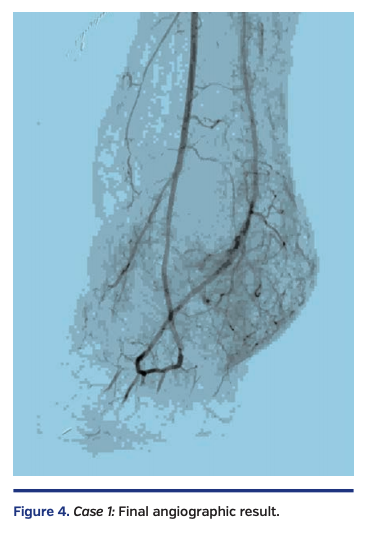

Due to residual eccentric disease in the anterior tibial and dorsalis pedis arteries, atherectomy was performed with the same device from the anterior tibial into the posterior tibial via the pedal arch, followed by balloon angioplasty with a 2.5 x 220 mm Coyote balloon (Boston Scientific), resulting in 0% residual stenosis and restoration of normal flow in the pedal arch (Figure 4).

The patient was subsequently discharged home with a healthy surgical site (Figure 1, right) and was able to ambulate with a cane.